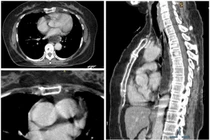

BSCKII Nguyễn Trần Anh Thư, khoa Ung Bướu, Trung tâm Ung Bướu, cho biết kết quả chụp MRI sọ não ghi nhận bà Hoa có khối u lớn 2,5 cm ở vùng trán - đỉnh bên phải gây phù não lan rộng và chèn ép sừng trán não thất phải.

Tiểu não hai bên có hai nốt tổn thương cùng nhiều u nhỏ khác trong não (đa ổ). Các tổn thương này gây ra các triệu chứng khiến người bệnh nhầm lẫn là đột quỵ. Bác sĩ nghi ngờ các khối u ở não do ung thư di căn.

Kết quả chụp CT lồng ngực tiếp tục ghi nhận thùy trên phổi trái của bà Hoa có khối tổn thương kích thước hơn 7 cm, bờ gồ ghề, gây xẹp phổi xung quanh.